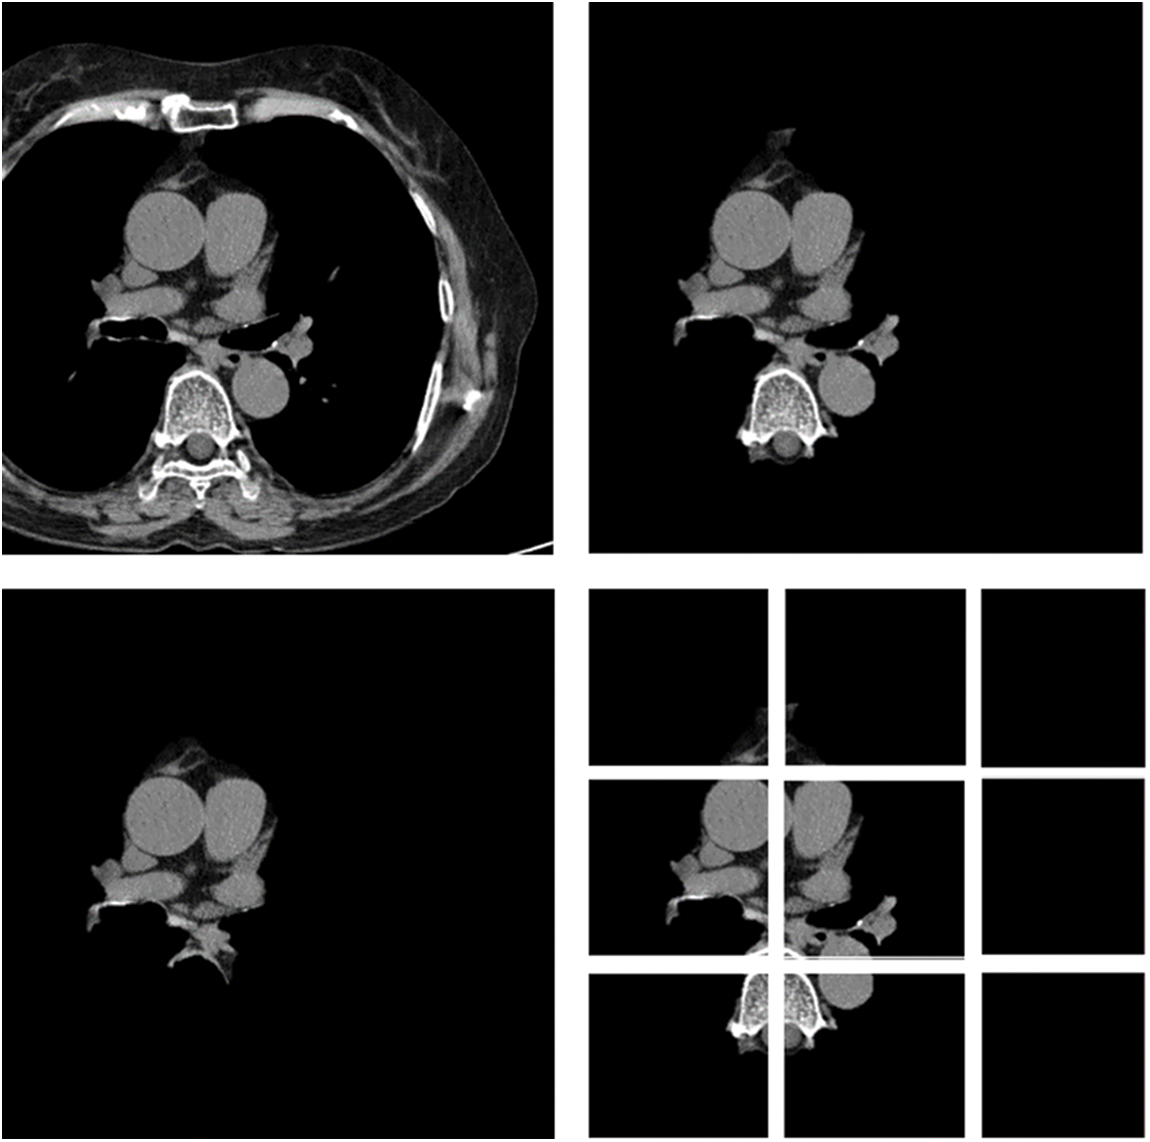

In this paper, first, a 512 × 512-sized CT image was read based on its HU pixels, and all of these HU pixels were converted to grayscale pixels and standardized, after which demarcation for parts such as the heart and fossa could be drawn [25,26]. Now, to remove the spine and ribs, the brightness of the bones such as the spine is stronger than the background and heart, so I adjusted the threshold and removed it using K-means clustering. However, while there are data in which the spine was properly removed from the image, in some other data, only the ribs were removed or a part of the heart was removed. Even when learning with these data, significant results were shown, and to supplement this, it was decided to use Grabcut [27] in this paper. The GrabCut algorithm extracts the image corresponding to the foreground, not the background, from the image, and extracts it step by step through interaction with the user. In this paper, by using Grabcut and considering the difference between the remaining bones and adjacent pixels between the heart, the heart and the bone were cut into two groups, which could reduce the amount of unnecessary information used. Fig. 8 shows the original data and each preprocessed data sample. Each data set was trained by deep learning models, and the parameters of each model are listed in Table 1. Resnet 50 has a total of 1.46 million parameters, Inception resnet v2 has 23.53 million parameters, and VGG has 1.1825 million parameters.

Figure 8: Data sample of original artery calcium score CT-data; cardiac segmented data; cardiac segmented data2; cropped data